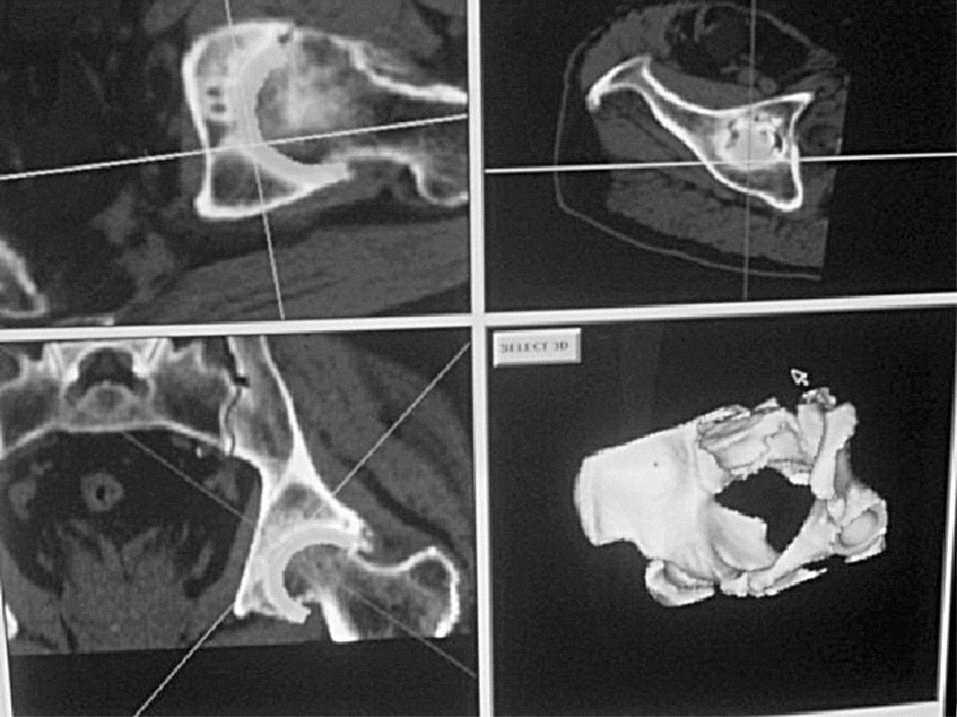

Realizamos un estudio retrospectivo comparativo durante dos años entre 42 pacientes a los que se les colocó una prótesis de cadera con acetábulo elíptico. En un grupo de 21 pacientes se utilizó un sistema de navegación, Surgigate System® (Medivision, Oberdorf, Suiza), y en otro, con el mismo número de pacientes, la técnica habitual con guías intraoperatorias manuales. La intervención se realizó por el mismo equipo quirúrgico. En todos los casos los pacientes fueron intervenidos de artroplastia primaria de cadera, afectos de coxartrosis esencial y en los cuales no se presentó ningún tipo de complicaciones técnicas intraoperatorias. Los dos grupos fueron semejantes en cuanto a peso, edad y sexo. En todos ellos se utilizó el mismo implante: cotilo elíptico Hedrocel® (Stratec, Oberdorf, Suiza), con vástago Metabloc® (Centerpulse, Suiza). En el grupo intervenido con la técnica estándar se usaron guías de orientación acetabular y planificación preoperatoria con plantillas. En el grupo con navegación la planificación se realiza previamente con TAC, que es informáticamente transferida al navegador. A continuación se eligió el tamaño del implante que mejor se adaptaba al tamaño óseo y, por último, se colocó el implante virtual en la posición deseada en los tres planos del espacio (anteversión, inclinación y profundidad), con una precisión máxima de 1° (fig. 2). En todos los casos se realizó una planificación de 40°-45° de inclinación y una anteversión comprendida entre 15° y 20°, según se adaptara mejor a la morfología ósea del paciente.

Figura 2. Planificación virtual con tomografía axial computarizada.